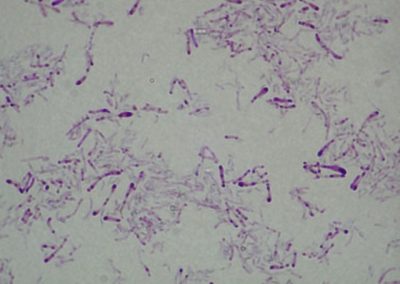

Bacillus anthracis

Rod Bacillus: Bacillus anthracis, kult.

Rod Bacillus: Bacillus anthracis, kuž.